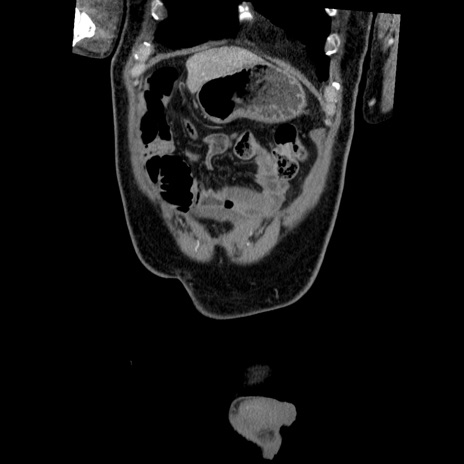

横断像

【症例】50歳代男性

【主訴】腹痛

【現病歴】AVMからの被殻出血のため回復期リハ病棟入院中。 本日午後3時頃急に下腹部痛が出現した。

【既往歴】AVM、被殻出血、虫垂炎、高血圧

【身体所見】意識晴明、左半身不全麻痺、会話の理解は良好、36.5°C、腹部:膨隆、全体に板状硬、下腹部正中に圧痛点あり、反跳痛-、筋性防御不明、右下腹部にope scar

【データ】WBC 9400、CRP 0.06